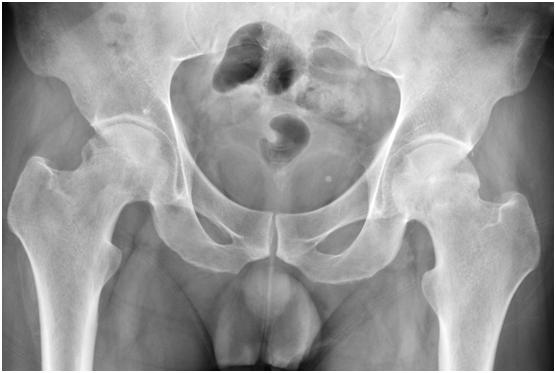

乙醇摄入是引起骨坏死的一个重要原因。

从临床资料看,乙醇引起骨坏死的发病率较激素低得多,据韩国调查在0.1%左右,中日友好医院骨坏死中心资料显示,自饮酒开始至发生骨坏死(临床就诊)最短者5年,多数骨坏死患者都经历了10~20年或更长的饮酒时间。

酒精性骨坏死后期往往出现塌陷,患者髋关节疼痛难忍,活动受限,无法正常行走,严重影响生活质量,常常需要做全髋关节置换手术治疗。